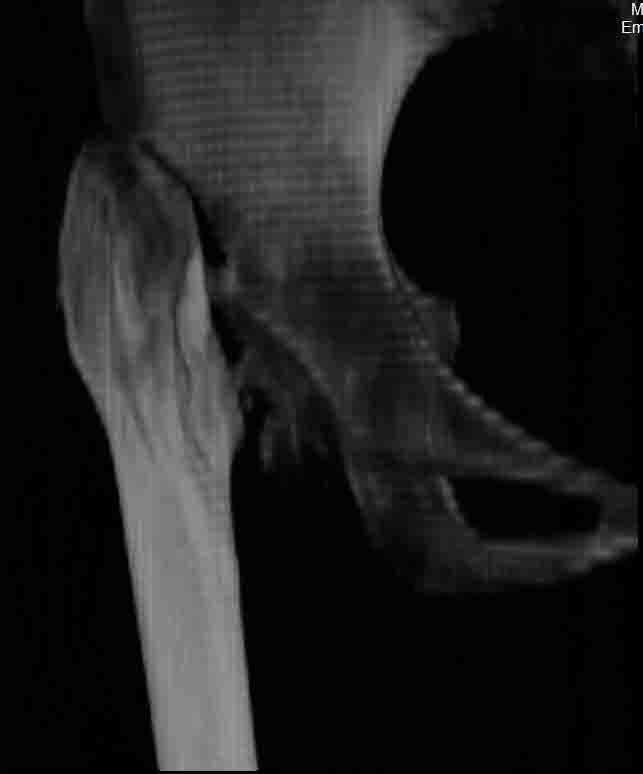

Сделал ей КТ.

С удивлением узнала, что перелом в области шейки у неё не сросся, хотя на рентгенограмме тех лет так оно и есть.

КТ - во вложении.

Интересна функциональная адаптация - практически полная функция того, что раньше было тазобедренным суставом.